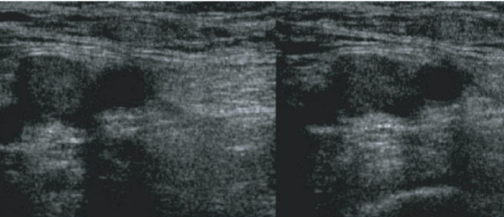

DVT in the common femoral vein. Unable to compress vein and there is a visible clot.

| current | 17:09, 1 November 2015 | ![]() | 504 × 217 (131 KB) | Neil.m.young (Talk | contribs) | DVT in the common femoral vein. Unable to compress vein and there is a visible clot. |